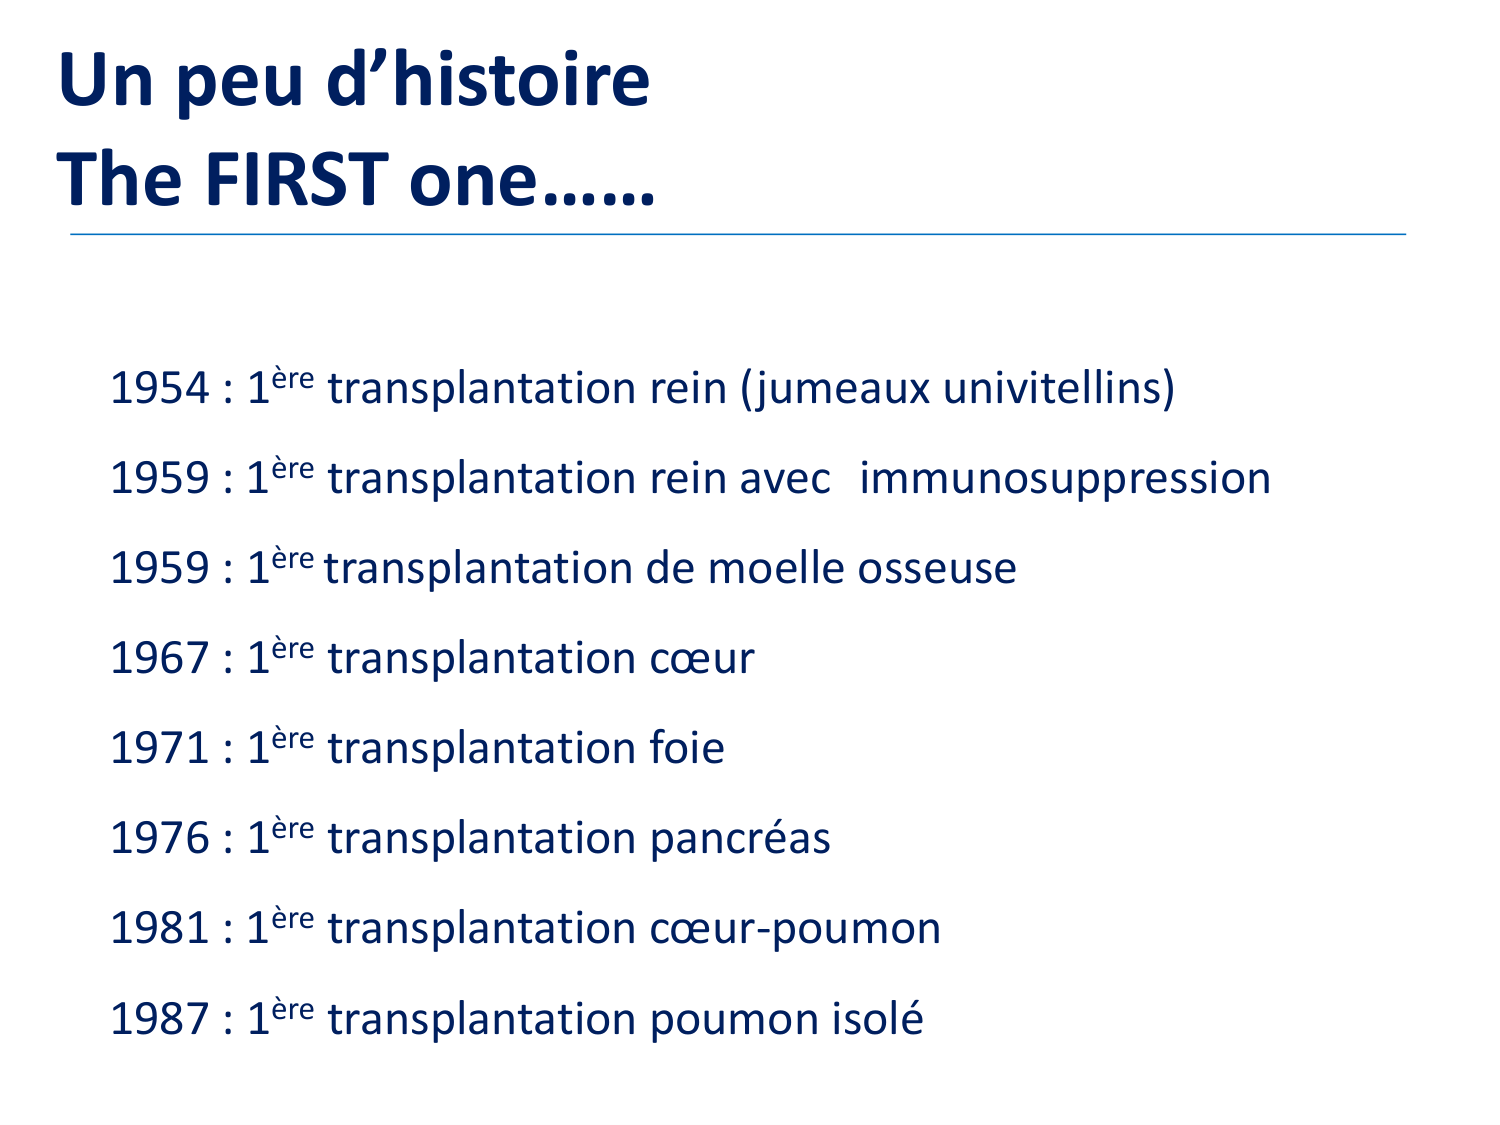

SMB4 Systèmes physiologiques 2 Immunologie, inflammation, transplantation · 61 pages · 8 sections